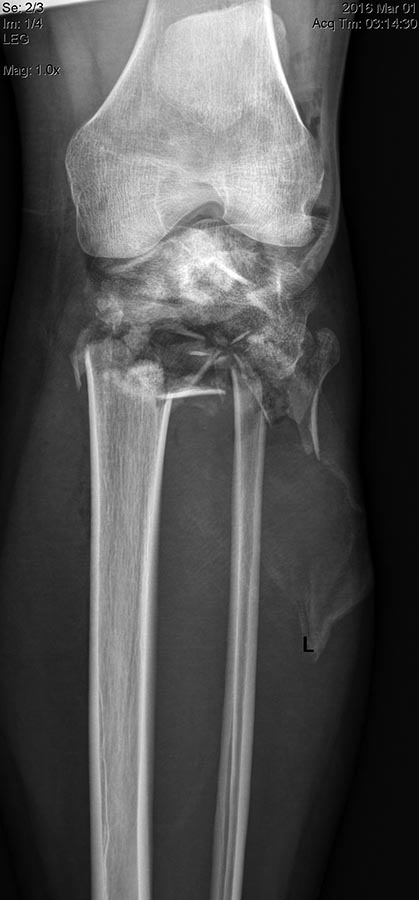

Имеется: Закрытый перелом диафиза левой локтевой кости. Закрытый оскольчатый перелом диафиза левой бедренной кости в средней трети. Открытые (3a-b) оскольчатые внутрисуставные переломы проксимального отдела обеих костей правой и левой голени. (см. снимки)

При поступлении выполнено: ПХО открытых перелом костей правой и левой голени, фиксация в аппаратах; фиксация перелома левой бедренной кости в аппарате; иммобилизация левого предплечья лонгетой.